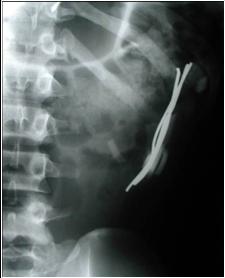

Pieces o’ hanger

Pieces o’ glass